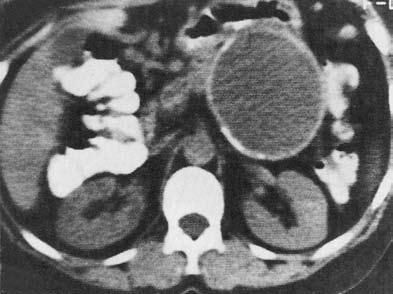

Ценным, хотя и более дорогим, методом диагностики панкреатических кист является КТ, дополняющая УЗИ (рис. 162, 163).

Оба этих метода помогают дифференцировать кистоподобные образования ПЖ от кистозного или опухолевого поражения других рядом расположенных органов, прежде всего почек и надпочечников. Под контролем УЗИ или КТ осуществляется и диагностическая пункция кист через переднюю брюшную стенку для исследования их содержимого (биохимический анализ, в том числе на ферменты ПЖ, цитологическое исследование осадка, микробиологическое исследование).

Рис. 163. Компьютерная томография. Псевдокиста поджелудочной железы